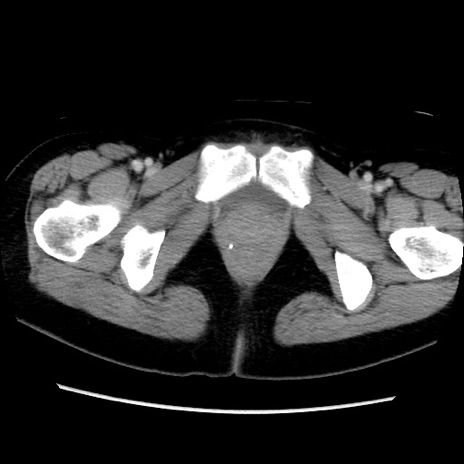

MRI(4日後)

【症例】40歳代女性

【主訴】上下腹部痛

【現病歴】2日目から下腹部痛あり。夜間は痛みで眠れなかった。昨日より上腹部痛と下痢が出現。臥位で痛みは軽快したため、休んでいた。本日になって臥位でも立位でも痛みが強くなってきたため救急要請。

【既往歴】子宮内膜症

【身体所見】部:平坦・軟、左上下腹部に圧痛あり、反跳痛あり。

【データ】WBC 21800、CRP 26.78